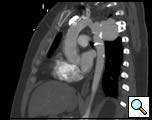

The patient is a 33 year old male with a history of juxtaductal coarctation who underwent a repair early in infancy. The patient had a recurrence of the coarctation and underwent a second open repair and left diaphragm plication at 2 years of age. He was lost to follow-up until recently when he presented to an emergency room with a several week history of hemoptysis and left back pain. The patient’s physical exam was remarkable only for a well-healed left thoracotomy incision. The patient was afebrile with equal blood pressures in all 4 extremities. The patient’s white count was normal. A CT scan of the chest demonstrated a saccular aneurysm of the proximal descending thoracic aorta measuring approximately 6cm in diameter (Figure 1). The patient was transferred to the Oregon Health and Sciences University for further management.